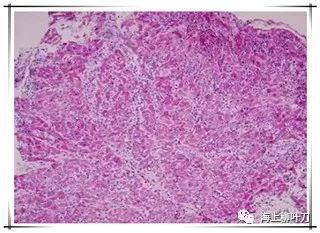

6.這是她的心肌病理切片,放大了100倍。

7.100倍還不是看得很清楚,放大400倍就很明顯了,一個個藍(lán)點就是淋巴球。這是很厲害的猛暴性心肌炎,整個心臟都被淋巴球浸潤了。